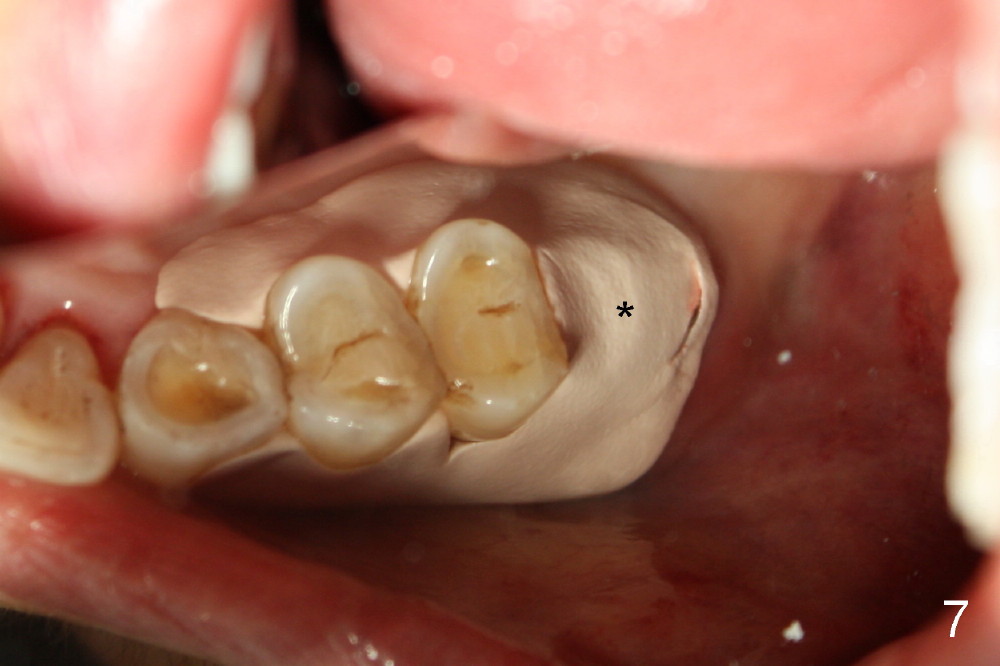

Extraction turns out to be simple with sectioning. After debridment of the socket and soaked with Clindamycin, the ostoeotomy forms using osteotomes, followed by insertion of a tap (Fig.4 T, 6x14 mm). After adjustment of the trajectory (Fig.4 arrow), larger taps are used (7x14, 8x14 mm) before placement of a 8x14 mm implant (Fig.5 I). There is small gap (Fig.6 arrowheads) around the implant. The wound is protected by perio dressing (Fig.7). The dressing is removed 7 days postop. Fig. 8 taken 2 weeks postop shows that the peri-implant gap has closed.

Crown is cemented 5.5 months postop.(Fig.9) and has been in function for more than 34 months (Fig.10,11).